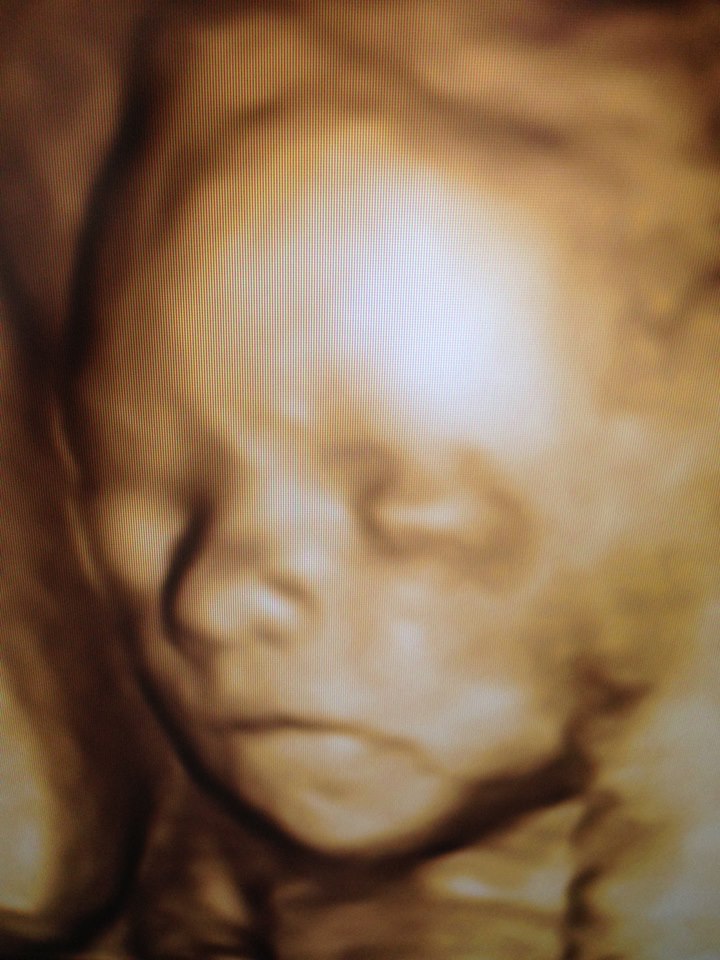

- Gravidanza e principali patologie ostetriche, Ecografie ostetriche, Patologia ginecologica, Ecografia ginecologica. Infertilità.

Foto e Video